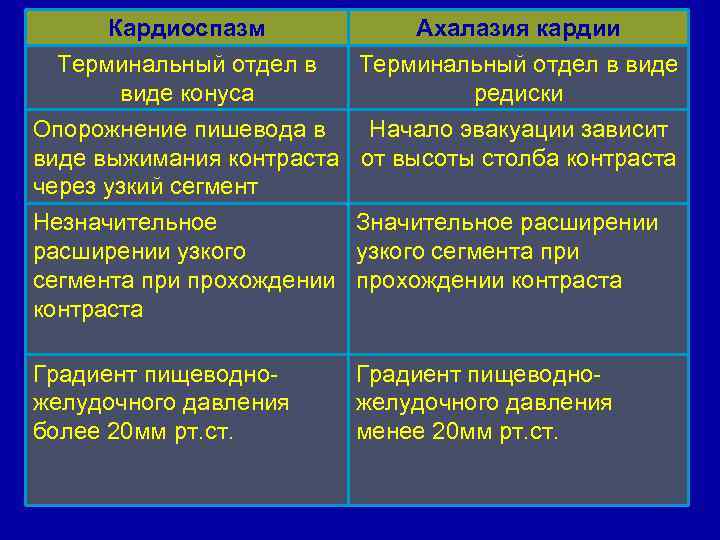

Кардиоспазм Ахалазия кардии Терминальный отдел в виде конуса редиски Опорожнение пишевода в Начало эвакуации зависит виде выжимания контраста от высоты столба контраста через узкий сегмент Незначительное Значительное расширении узкого сегмента при прохождении контраста Градиент пищеводножелудочного давления более 20 мм рт. ст. Градиент пищеводножелудочного давления менее 20 мм рт. ст.